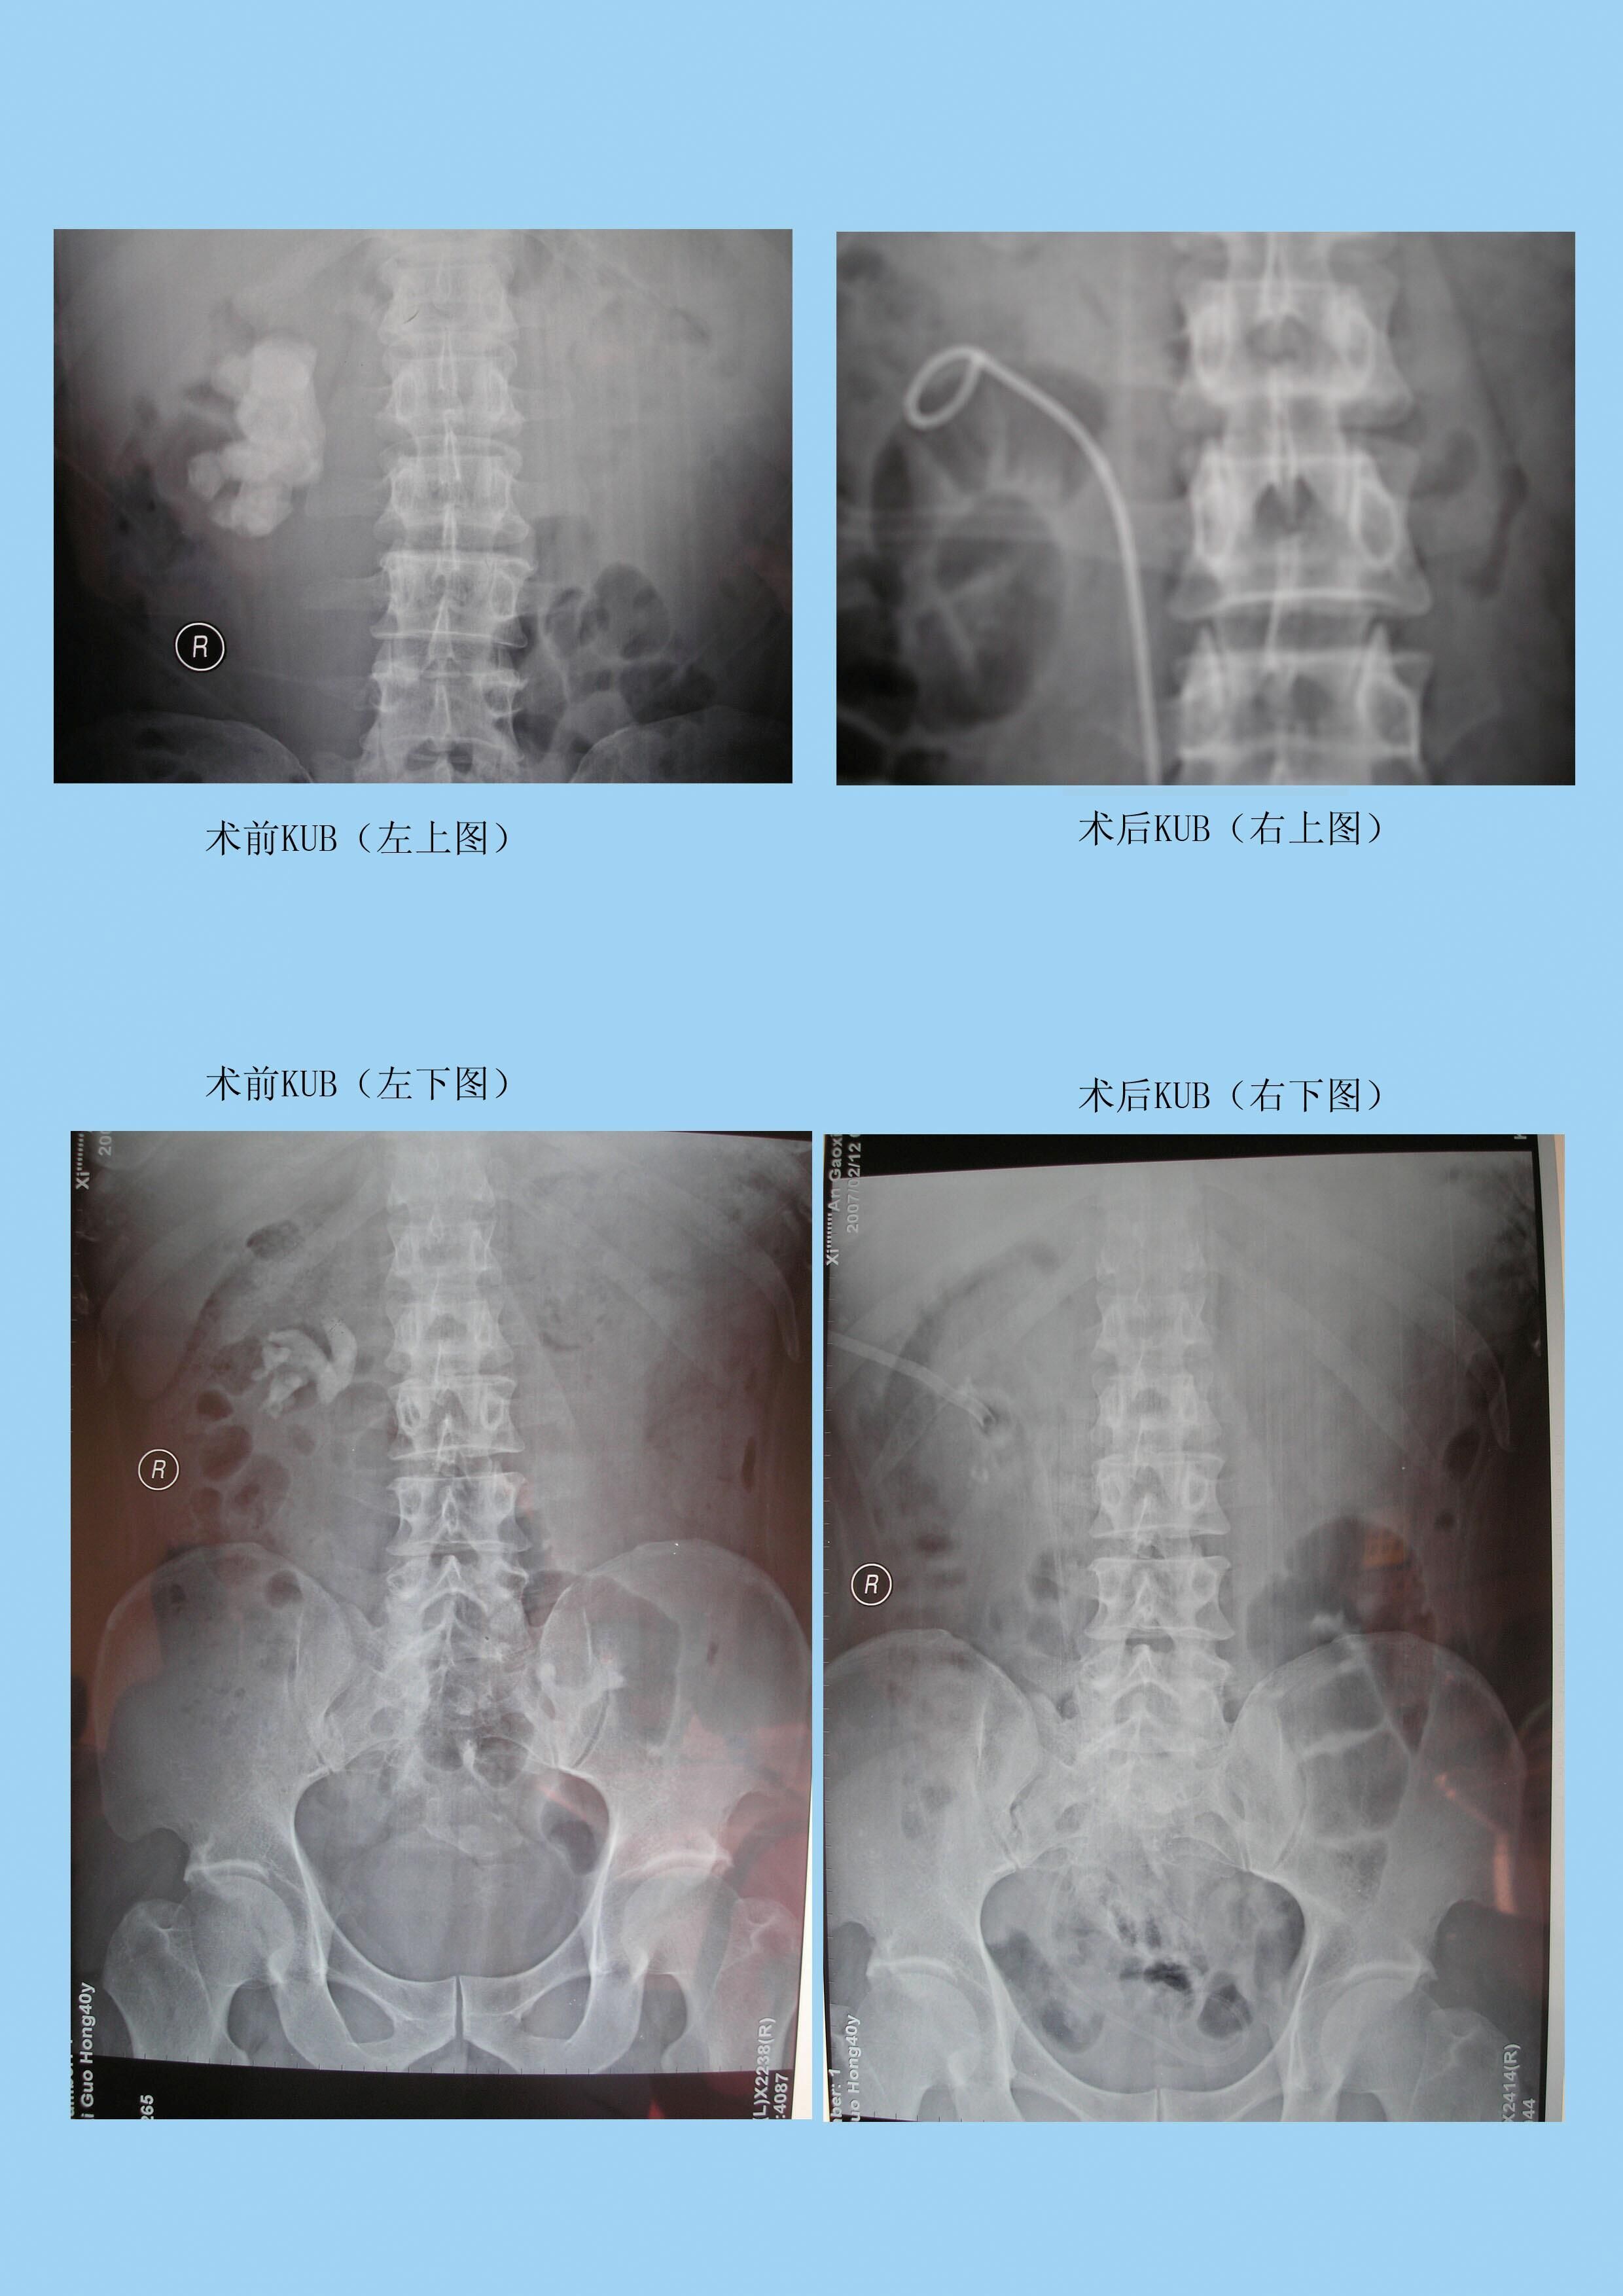

【微创经皮肾镜碎石取石术】

在B超或C型臂X线结合引导下,在腰部打一个5毫米大小的小孔,建立起皮肤至肾脏的通道,在经皮肾镜引导下结石显示于显示屏上采用钬激光或气压弹道对准结石,将结石瞬间汽化或粉碎为粉沫状,应用清石系统将粉沫结石吸出体外,又称为‘打洞取石’。

优势:不开刀、微创伤、痛苦小、出血少、恢复快、费用低、大大缩短住院时间,通常5-7天即可出院。

适应症:主要治疗疑难的巨大肾结石、多发肾结石、鹿角型肾结石、输尿管上段结石。